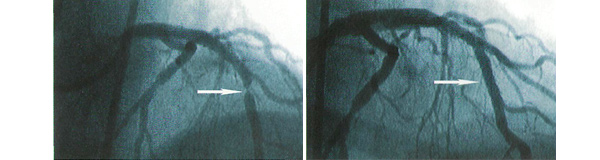

Стентирование коронарных артерий сердца. Стентирование сердца форум. Стентирование сердца форум. Стентирование ов расшифровка. Стентирование сердца форум.

Стентирование коронарных артерий. Стентирование коронарных артерий сердца. Стентирование сердца форум. Коронографияистэнтирование. Стентирование сердца форум.

Инфаркт миокарда стентирование. Стентирование коронарных артерий. Стентирование коронарных артерий. Что такое стентирование пмжв лка. Первичная транслюминальная ангиопластика.